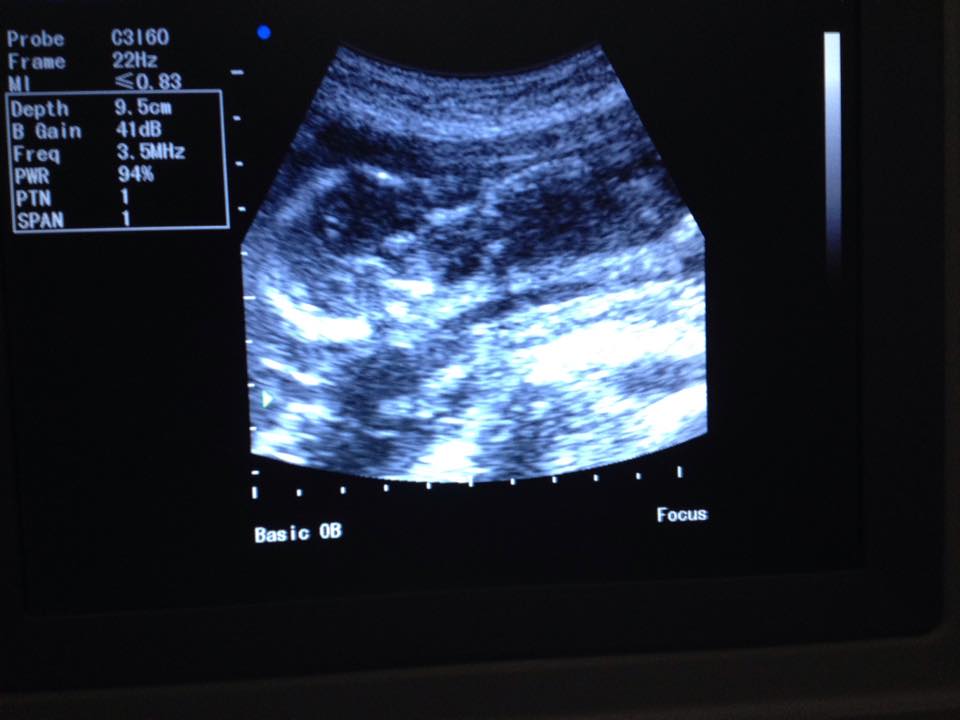

After arrival, Matthew met us at the plane and we immediately met Shannon at the hospital and began the ultrasound. Shannon struggled to find the baby in a still-enough position to get a heart beat, so it was no wonder I was unable to do it myself! But, we got not only a normal heartbeat, but also good measurements and looks at the essential organs to know that baby is doing well. (We prefer to find out gender at birth, plus it was a bit early.) Baby moved almost constantly, but I never felt a thing!